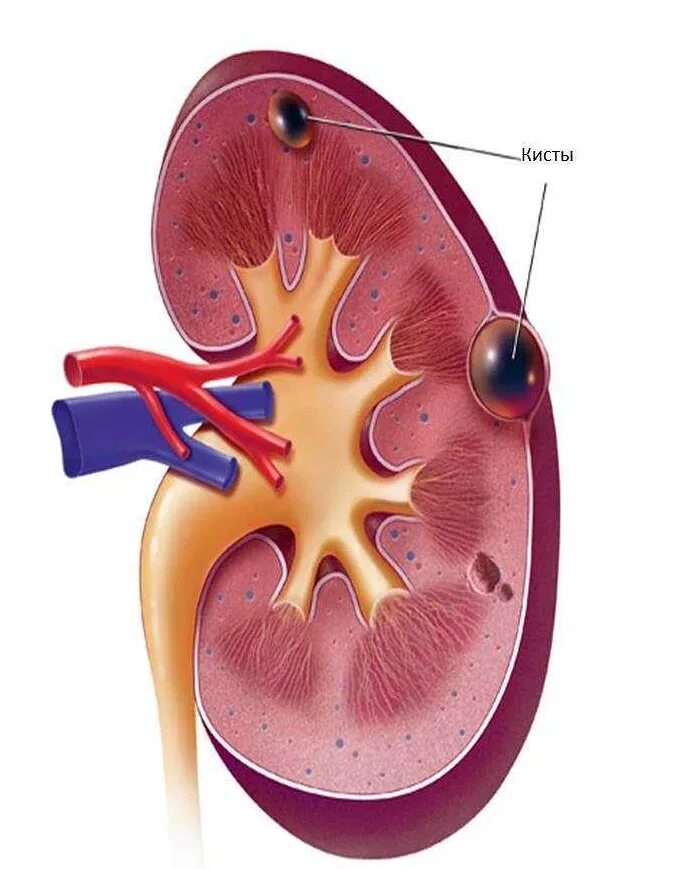

Можно ли вылечить кисту почки